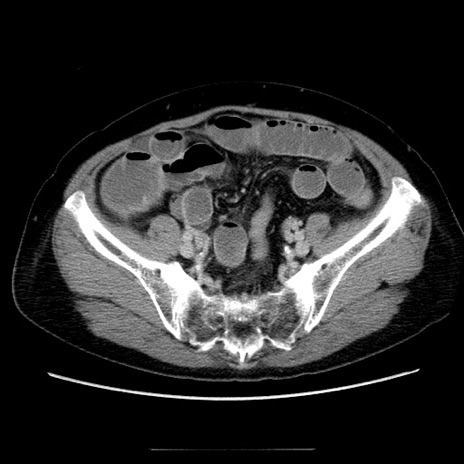

症例5(横断像)

【症例】70歳代女性

【主訴】お腹が張る

【現病歴】1週間くらい前から腹部膨満の自覚あり。昨日夜から増悪したため、本日救急外来受診。

【身体所見】意識清明、BT 36.5℃、BP 165/106mmHg、HR 80bpm、SpO2 98%、腹部:膨満、軟、自発痛・圧痛なし、触診にて不快感あり、腸蠕動音:減弱

【データ】WBC 12600、CRP 1.04